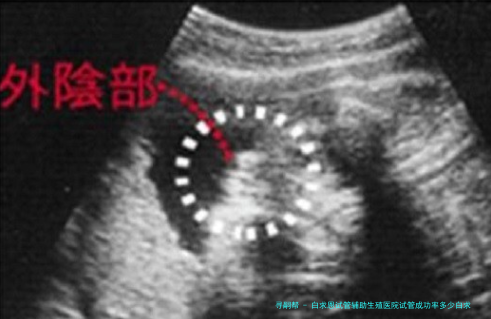

白求恩试管辅助生殖医院试管婴儿成功率解读:白求恩试管辅助生殖医院试管成功率是很很好。白求恩国际试管辅助生殖医院做试管的移植成功率在40%-50%左右,不过在该院做试管移植的成功率因人而异,一般年龄小于35岁的病患普遍做试管的成功率要高一些,关于高龄的病人来讲试管移植的成功率可能会少于50%,因而做试管移植的成功率需要结合自己的情况来看。

白求恩国际试管辅助生殖医院的试管婴儿成功率相当高。根据此医院的统计数据,他们的成功率保持在40%-50%左右,有些患者身体情况好,成功率会超过60%,这一成功率放置于整个河北试管婴儿医院排名榜中都是无比可观的,至于石家庄市的病患来讲,有须要的可以放心到此医院助孕。

白求恩试管辅助生殖医院试管成功率是很挺好的,总体来说稳固在40%-50%左右,关于患者来讲,这样的成功率已然是很不错的了,只是做试管的成功率只可作为参考,病患个人情况会影响到最终的受孕率,个人状况越好的话,成功率则会更高。